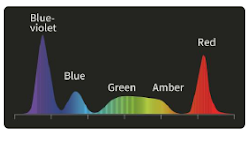

Технология многоспектрального композитного формирования изображения:

5 независимо управляемых высокоточных светодиодов обеспечивают работу специальных световых режимов для решения различных клинических задач в процессе диагностики и лечения.

Специальные оптические режимы:

Двухцветная визуализация (DSI)

Двухцветная визуализация (DSI)

Выявление и классификация опухолевых образований, прогнозирование глубины инфильтрации.

DSI: Двухцветная визуализация

Слабая проницаемость и сильное рассеивание фиолетового и зеленого света позволяет хорошо визуализировать морфологию кровеносных сосудов слизистой оболочки . Кроме того, свет в этих двух диапазонах легче всего поглощается гемоглобином, что уменьшает отражение и рассеивание и повышает контрастность между кровеносными сосудами и окружающей тканью.

Применение

- Точное обследование пораженных участков слизистой.

- Определение инфильтрации и границы пораженного участка.

- Выявление и классификация опухолевых образований.

Белый свет

DSI